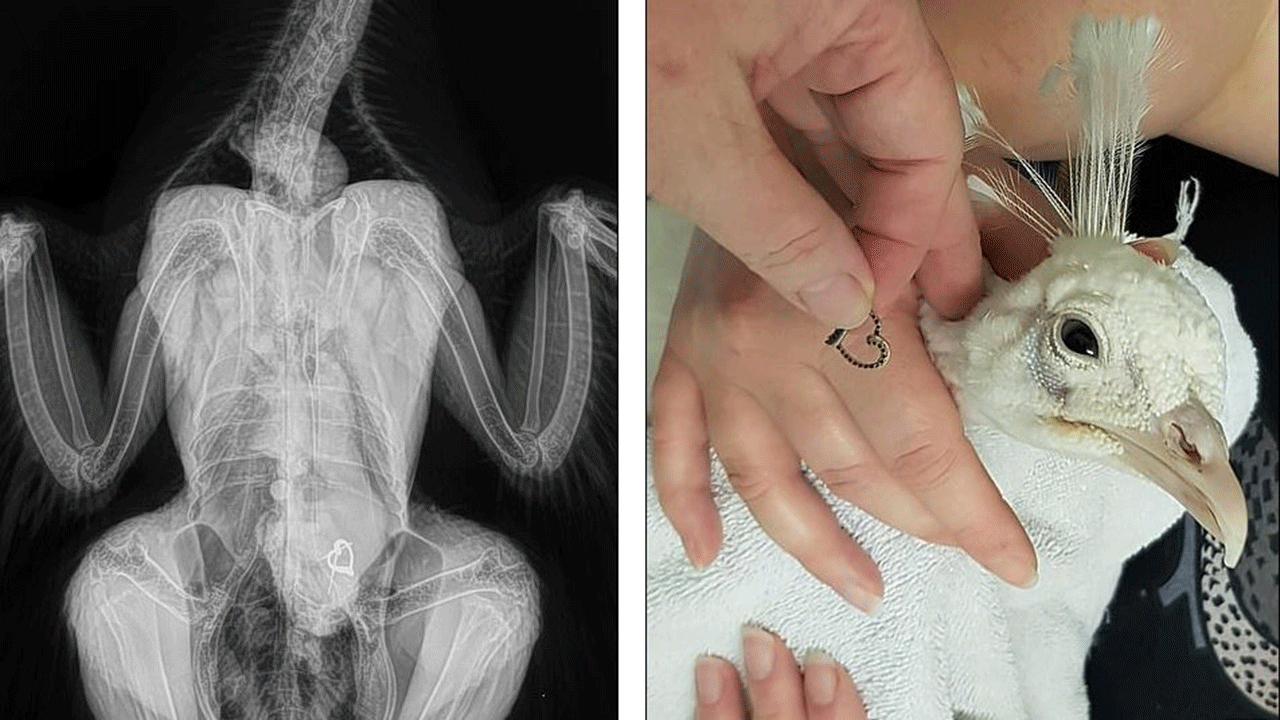

شاركت عيادات بيطرية صورا لأشعة سينية خاصة بحيوانات، تظهر أغرب الأشياء التي قامت الحيوانات بابتلاعها.

وتنوعت الأشياء التي استخرجها الأطباء البيطريون من معدة الحيوانات بين الألعاب والمصابيح الكهربائية، والعملات المعدنية.